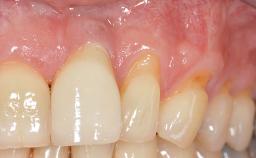

Periodontal Plastic Surgery and Prosthetic Procedures to Treat Peri-Implant Soft-Tissue Dehiscences

A 30-year-old woman was referred by her general dentist for evaluation of an esthetic complication related to previous implant treatment for congenitally missing maxillary lateral incisors. The patient’s chief complaint was the inadequate esthetic appearance of her smile. The case demonstrates the use of a combined approach to achieve optimal results. Two different flap designs - a tunnel technique and a coronally advanced flap - are employed based on the surgical objectives for the affected site.

Soft Tissue Contour and Volume Slightly compromised